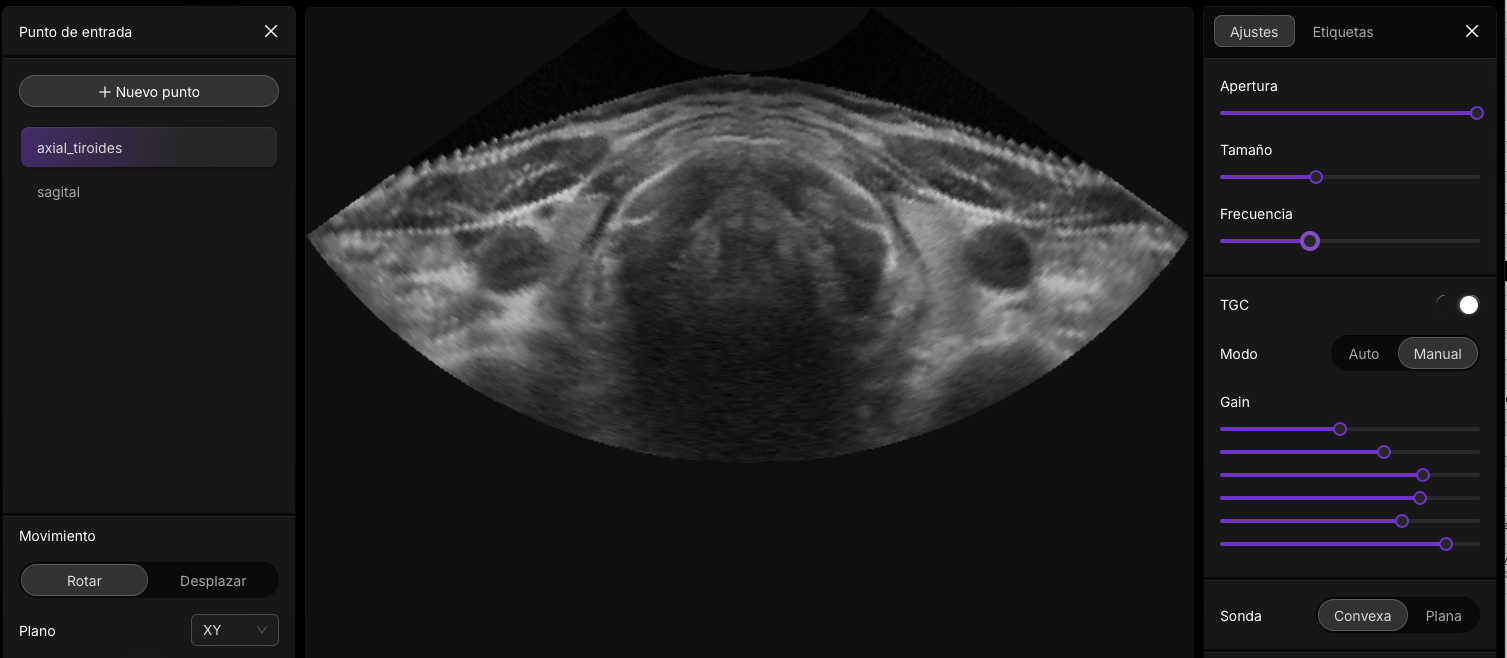

Esta intefaz de usuario, la podras encotnar en el modulo del curso II: Parametros nivel avanzado ( pronto)

Presets en Ecografía

Los presets ecográficos son configuraciones preestablecidas en los equipos de ultrasonido que están diseñadas para optimizar la calidad de la imagen según el tipo de estudio que se realizará. Cada preset ajusta parámetros clave como la frecuencia del transductor, la profundidad de escaneo, la ganancia (brillo general de la imagen), el enfoque y los filtros, de manera que las imágenes obtenidas sean adecuadas para el área anatómica en cuestión. Por ejemplo, al realizar un estudio abdominal, se seleccionará un preset que priorice una mayor profundidad de penetración y un menor nivel de detalle, ya que los órganos abdominales están situados más profundamente en el cuerpo. En contraste, un preset para estudios vasculares ajustará la configuración para captar flujos sanguíneos con mayor sensibilidad mediante modos Doppler y resoluciones más finas.

Optimización de Parámetros en Ecografía

La optimización de los parámetros en ecografía es clave para obtener imágenes de alta calidad, adaptadas a las necesidades clínicas y anatómicas específicas. Estos ajustes permiten al operador refinar la claridad, resolución y contraste de la imagen, lo que contribuye a un diagnóstico más preciso.

Ganancia

La ganancia es el ajuste que controla el brillo general de la imagen ecográfica al amplificar las señales recibidas por el transductor. Un aumento excesivo en la ganancia puede provocar imágenes demasiado brillantes y pérdida de detalles, mientras que una ganancia baja puede oscurecer las estructuras. Por ejemplo, al explorar tejidos abdominales profundos, una ganancia adecuada resalta los contornos de los órganos sin saturar la imagen. La ganancia es un control esencial que regula la intensidad de la señal de eco recibida y, en consecuencia, la luminosidad de la imagen en la pantalla. Al aumentar la ganancia, se amplifican los ecos de retorno, lo que hace que la imagen se vea más brillante. Por el contrario, disminuir la ganancia reduce el brillo, proporcionando una imagen más oscura. Un ajuste adecuado de la ganancia es crucial para diferenciar las estructuras anatómicas sin crear artefactos o distorsiones en la imagen. Este parámetro ayuda a compensar la atenuación del ultrasonido en tejidos más profundos. La ganancia regula la intensidad de la señal de eco recibida y, en consecuencia, la luminosidad de la imagen en la pantalla. Al aumentar la ganancia, se amplifican los ecos de retorno, haciendo que la imagen se vea más brillante. Disminuirla reduce el brillo, proporcionando una imagen más oscura. Este ajuste es crucial para diferenciar las estructuras anatómicas sin crear artefactos o distorsiones, especialmente en tejidos profundos donde la señal puede atenuarse.

Compensación de Ganancia por Tiempo (TGC)

La compensación de ganancia por tiempo (TGC) ajusta la ganancia de forma independiente a diferentes profundidades, ayudando a mejorar la uniformidad de la imagen al corregir la atenuación del ultrasonido en tejidos más profundos. Esto garantiza una visualización clara tanto de las estructuras superficiales como profundas, optimizando la calidad de la imagen.